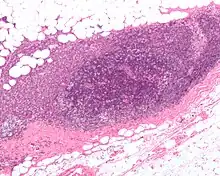

High-grade invasive ductal carcinoma, with minimal tubule formation, marked pleomorphism, and prominent mitoses, 40x field

Micrograph showing a lymph node invaded by ductal breast carcinoma, with an extension of the tumor beyond the lymph node

- Histopathology. Breast cancer is usually classified primarily by its histological appearance. Most breast cancers are derived from the epithelium lining the ducts or lobules, and these cancers are classified as ductal or lobular carcinoma. Carcinoma in situ is growth of low-grade cancerous or precancerous cells within a particular tissue compartment such as the mammary duct without invasion of the surrounding tissue. In contrast, invasive carcinoma does not confine itself to the initial tissue compartment.[135]

- Grade. Grading compares the appearance of the breast cancer cells to the appearance of normal breast tissue. Normal cells in an organ like the breast become differentiated, meaning that they take on specific shapes and forms that reflect their function as part of that organ. Cancerous cells lose that differentiation. In cancer, the cells that would normally line up in an orderly way to make up the milk ducts become disorganized. Cell division becomes uncontrolled. Cell nuclei become less uniform. Pathologists describe cells as well differentiated (low grade), moderately differentiated (intermediate grade), and poorly differentiated (high grade) as the cells progressively lose the features seen in normal breast cells. Poorly differentiated cancers (the ones whose tissue is least like normal breast tissue) have a worse prognosis.

The breast cancer grade is assessed by comparison of the breast cancer cells to normal breast cells. The closer to normal the cancer cells are, the slower their growth and the better the prognosis. If cells are not well differentiated, they will appear immature, will divide more rapidly, and will tend to spread. Well differentiated is given a grade of 1, moderate is grade 2, while poor or undifferentiated is given a higher grade of 3 or 4 (depending upon the scale used). The most widely used grading system is the Nottingham scheme.[194]